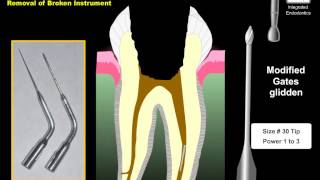

Removal of broken instrument video

Broken Instrument Removal

Broken Instrument Removal Removal of broken instrument

Removal of broken instrument Removal of a broken instrument with the tube technique